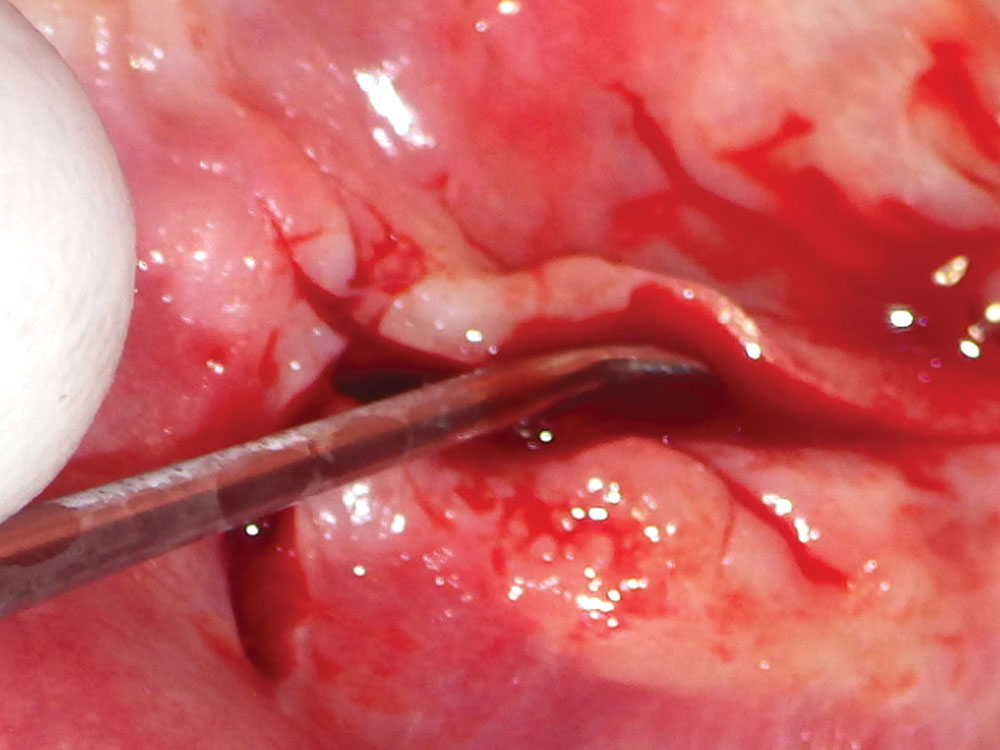

When exposing the recipient site, nontraumatic elevation of the tissue is required to obtain a full-thickness mucoperiosteal flap. This should include an uninterrupted release of the flap that includes the surface mucosa, submucosa and periosteum. As the tissue is reflected, the underlying bone should be scraped with a bone curette to remove any tissue. Ideally, a specialized periosteal elevator (e.g., 2/4 Molt Curette, Newport Surgical™ Implant and Bone Grafting Instrumentation Kit [Glidewell; Irvine, Calif.]) should be used with the curette edge resting on the bone to prevent tearing of the tissue flap (Fig. 7).

Tissue reflection: Use of a 2/4 molt curette, which allows for nontraumatic soft-tissue exposure

Figure 7: Tissue reflection: Use of a 2/4 molt curette, which allows for nontraumatic soft-tissue exposure.